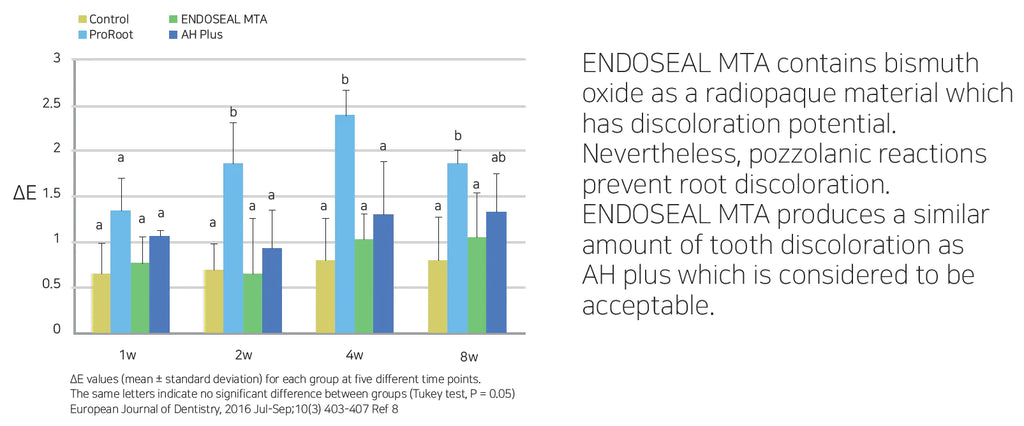

ENDOSEAL MTA is a paste-type root canal sealer based on pozzolan cement that has excellent physical and biological properties of MTA. It is premixed and pre-loaded in a syringe that allows direct application of the sealer into the root canal without requiring powder/liquid mixing, unlike other products. The product has outstanding flowability and maneuverability, which makes it possible to completely fill the root canal system including accessory and lateral canals. It is eugenol-free and will not impede adhesion inside the root canal.